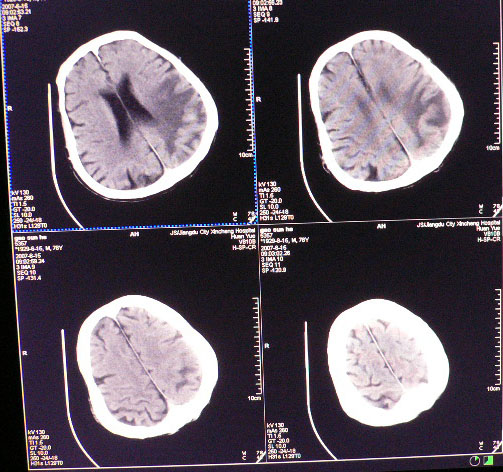

男性,78岁,失语,意识障碍1天

平扫ct值为40-45hu,增强为不均匀强化,ct值为81-85hu

皮层下厚壁花环状高密度影,明火显强化,大范围指样水肿,支持转移瘤诊断。其后上方好像还有小灶。

从发病部位,病灶强化特点、周围水肿情况支持脑转移瘤诊断,可进一步检查查找原发灶。